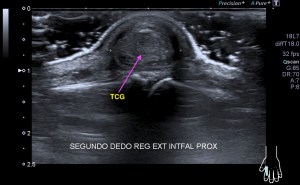

La radiografía revela aumento de las partes y se refrenda en la ecografía como puedes ver en la imagen aunque aún no hay afectación en el hueso en el caso que te presento hoy.

Ecografícamente y debido a su levedad, en el caso de hoy solo observamos cambios en las partes blandas de la cara lateral de la cabeza del quinto metatarsiano, este tejido se muestra heterogéneo, la cortical del hueso ligeramente prominente sin afectación de la misma.